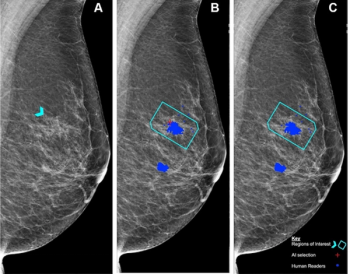

New research suggests the capability of a mammography-based deep learning model to identify women at high risk of breast cancer led to more than triple the cancer detection rate on breast MRI in comparison to traditional risk assessment tools.

In a prospective study of over 55,000 women who had screening mammography, researchers found that double-reading by a radiologist and artificial intelligence (AI) was non-inferior to double-reading by two radiologists in detecting breast cancer.

In separate test sets that included challenging mammography cases, researchers found that artificial intelligence (AI) demonstrated similar sensitivity and specificity for detecting breast cancer in comparison to assessments from over 500 clinicians.

The study demonstrated that the combined model yielded improved risk assessment for both interval and long-term breast cancers.